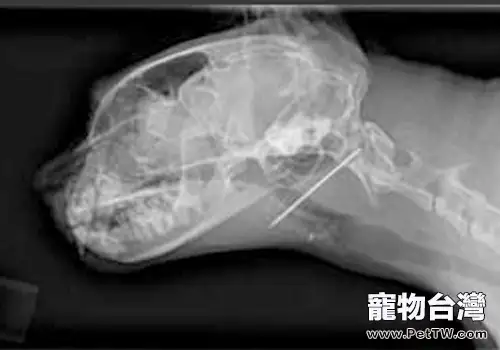

很多飼主對於咳嗽和喉部有異物仍不能很好的區分,當他們看到自己的貓咪出現咳嗽或者是乾嘔的情況,通常會認為是貓咪的喉部卡到了什麼東西。但是很多時候並非如此,要判斷貓咪的喉部是否有異物,不能僅僅靠咳嗽這一症狀來判斷。我們需要通過多項測試,有時候可能還需要通過X光片的照射才能夠很好地作出判斷。

一般光靠咳嗽是不能判斷貓咪的喉嚨是否卡住了異物。通常我們需要輕捏幾下貓咪的喉部,如果出現了疼痛症狀則有可能有異物的存在,而且我們要知道的是如果貓咪的喉部有異物的存在,那麼它們通常會因為嚥食時出現疼痛,從而停止進食。當它們經常流出口水做出痛苦狀時,它的喉部被魚骨刺扎的可能性極高。所以類似魚骨會細碎而容易刺扎喉部的骨頭,盡量不要餵食。即使要餵食,亦應先將骨頭去除為宜,以免發生不測。